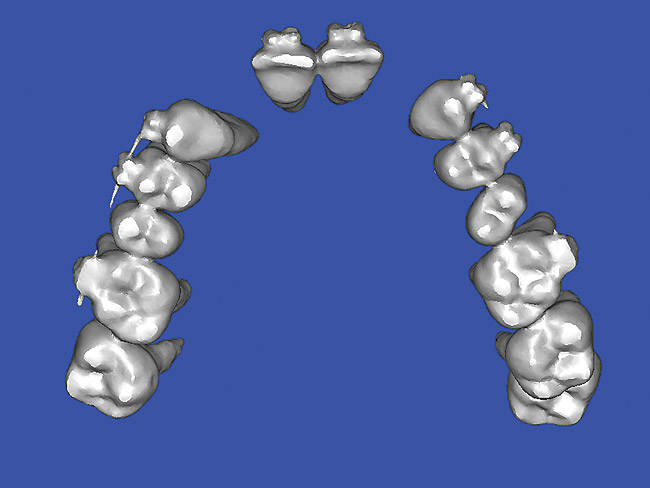

Using different masking (segmentation) and threshold Hounsfield unit values, several new 3D bone volumes can be created which offer invaluable information. To help determine the final position of each implant a new bone model was created with a Hounsfield unit value of 1480, which eliminated all but the densest objects included in the scan data. (Results may vary depending on the CBCT machine used.) The inner and outer layers of bone were removed, leaving the underlying enamel and root structure of the teeth (Figure 14). After the bone had been stripped away, the root inclinations were examined closely. The most striking findings confirmed the rotated position of the right central, while revealing the slight mesial dilaceration of the root apex, which converged on the space needed for the path of the potential implant (Figure 15). The schematic shapes of the proposed implants were visualized for the right and left lateral spaces in different rotations of the 3D maxillary arch. It was at this point that a determination was made as to the appropriate implant shape and type that would fit the available space while avoiding encroachment on adjacent tooth roots. A tapered design implant (Tapered Screw-Vent®, Zimmer Dental, www.zimmerdental.com) was chosen from the large virtual library. With the SIMPlant software, the virtual library contains data from dozens of implant manufacturers and realistic computer-aided design representations as seen in Figure 16 through the translucent bone. The position of the left implant can be visualized with adequate mesial-distal distance between adjacent tooth roots (Figure 17) and a more delicate placement (Figure 18).

Figure 16  SOFTWARE IMAGING Virtual implants were placed to determine the appropriate shape and type for the available space, in this case a tapered design allowed for adequate mesial-distal distance between adjacent roots.

Figure 16

Figure 17   SOFTWARE IMAGING Virtual implants were placed to determine the appropriate shape and type for the available space, in this case a tapered design allowed for adequate mesial-distal distance between adjacent roots.

Figure 17

Figure 18   SOFTWARE IMAGING Virtual implants were placed to determine the appropriate shape and type for the available space, in this case a tapered design allowed for adequate mesial-distal distance between adjacent roots.

Figure 18